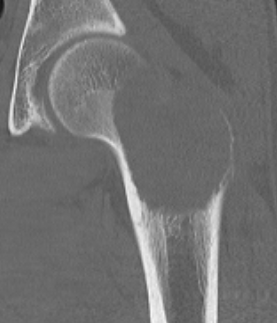

Brown's tumour

Brown's tumour in hyperparathyroidism

- consider Brown's tumours / hyperparathyroidism

- histology findings very similar